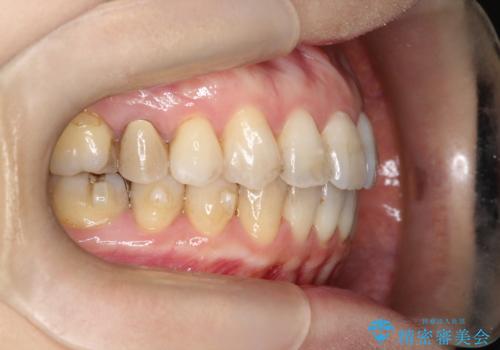

【インビザライン 】前歯を下げたい

- 前歯の凸凹と、前突を主訴に来院されました。

インビザライン にて治療を行なっております。

治療期間中はゴムかけを行なってもらうことで、前歯を下げることができました。